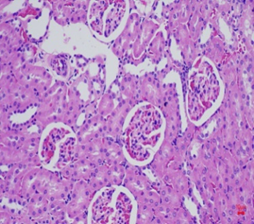

Hình thái vi thể thận, lách chuột ở cả ba lô đều bình thường, không có sự khác biệt so với hình ảnh vi thể thận, lách chuột ở lô chứng. Các tế bào ống thận bắt màu xanh thẫm. Cấu trúc các vùng chức năng thận, lách bình thường (Hình 3, 4).

![]() | ![]() | ![]() |

Hình 3. Vi thể thận chuột dưới kính hiển vi khuếch đại 200 lần sau 28 ngày uống Probiotic EntVN 500 mg. A- lô chứng; B- lô trị 1; C- lô trị 2